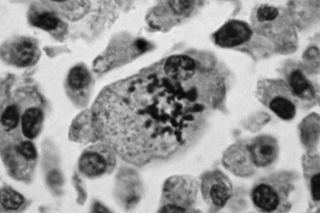

Why are early-onset cancers specifically concerning? Typically, cell damage begins after the age of 50, which is a risk factor for cancer. Cancers in people younger than that aren’t necessarily ruled out, but rising rates in a demographic that shouldn’t typically be susceptible to the disease indicates something deeper is going on – it is possible that early-onset cancers could be biologically different from typical cancers. “Some of the molecular characteristics and pathways of how something becomes cancerous are different between the older and younger groups… Younger adults tend to have a more aggressive-appearing cancer. They also tend to present at a more advanced stage that is not solely explained by a delay in diagnosis,” said Jeremy Kortmansky, MD, a Yale Medicine medical oncologist specializing in gastrointestinal cancers.